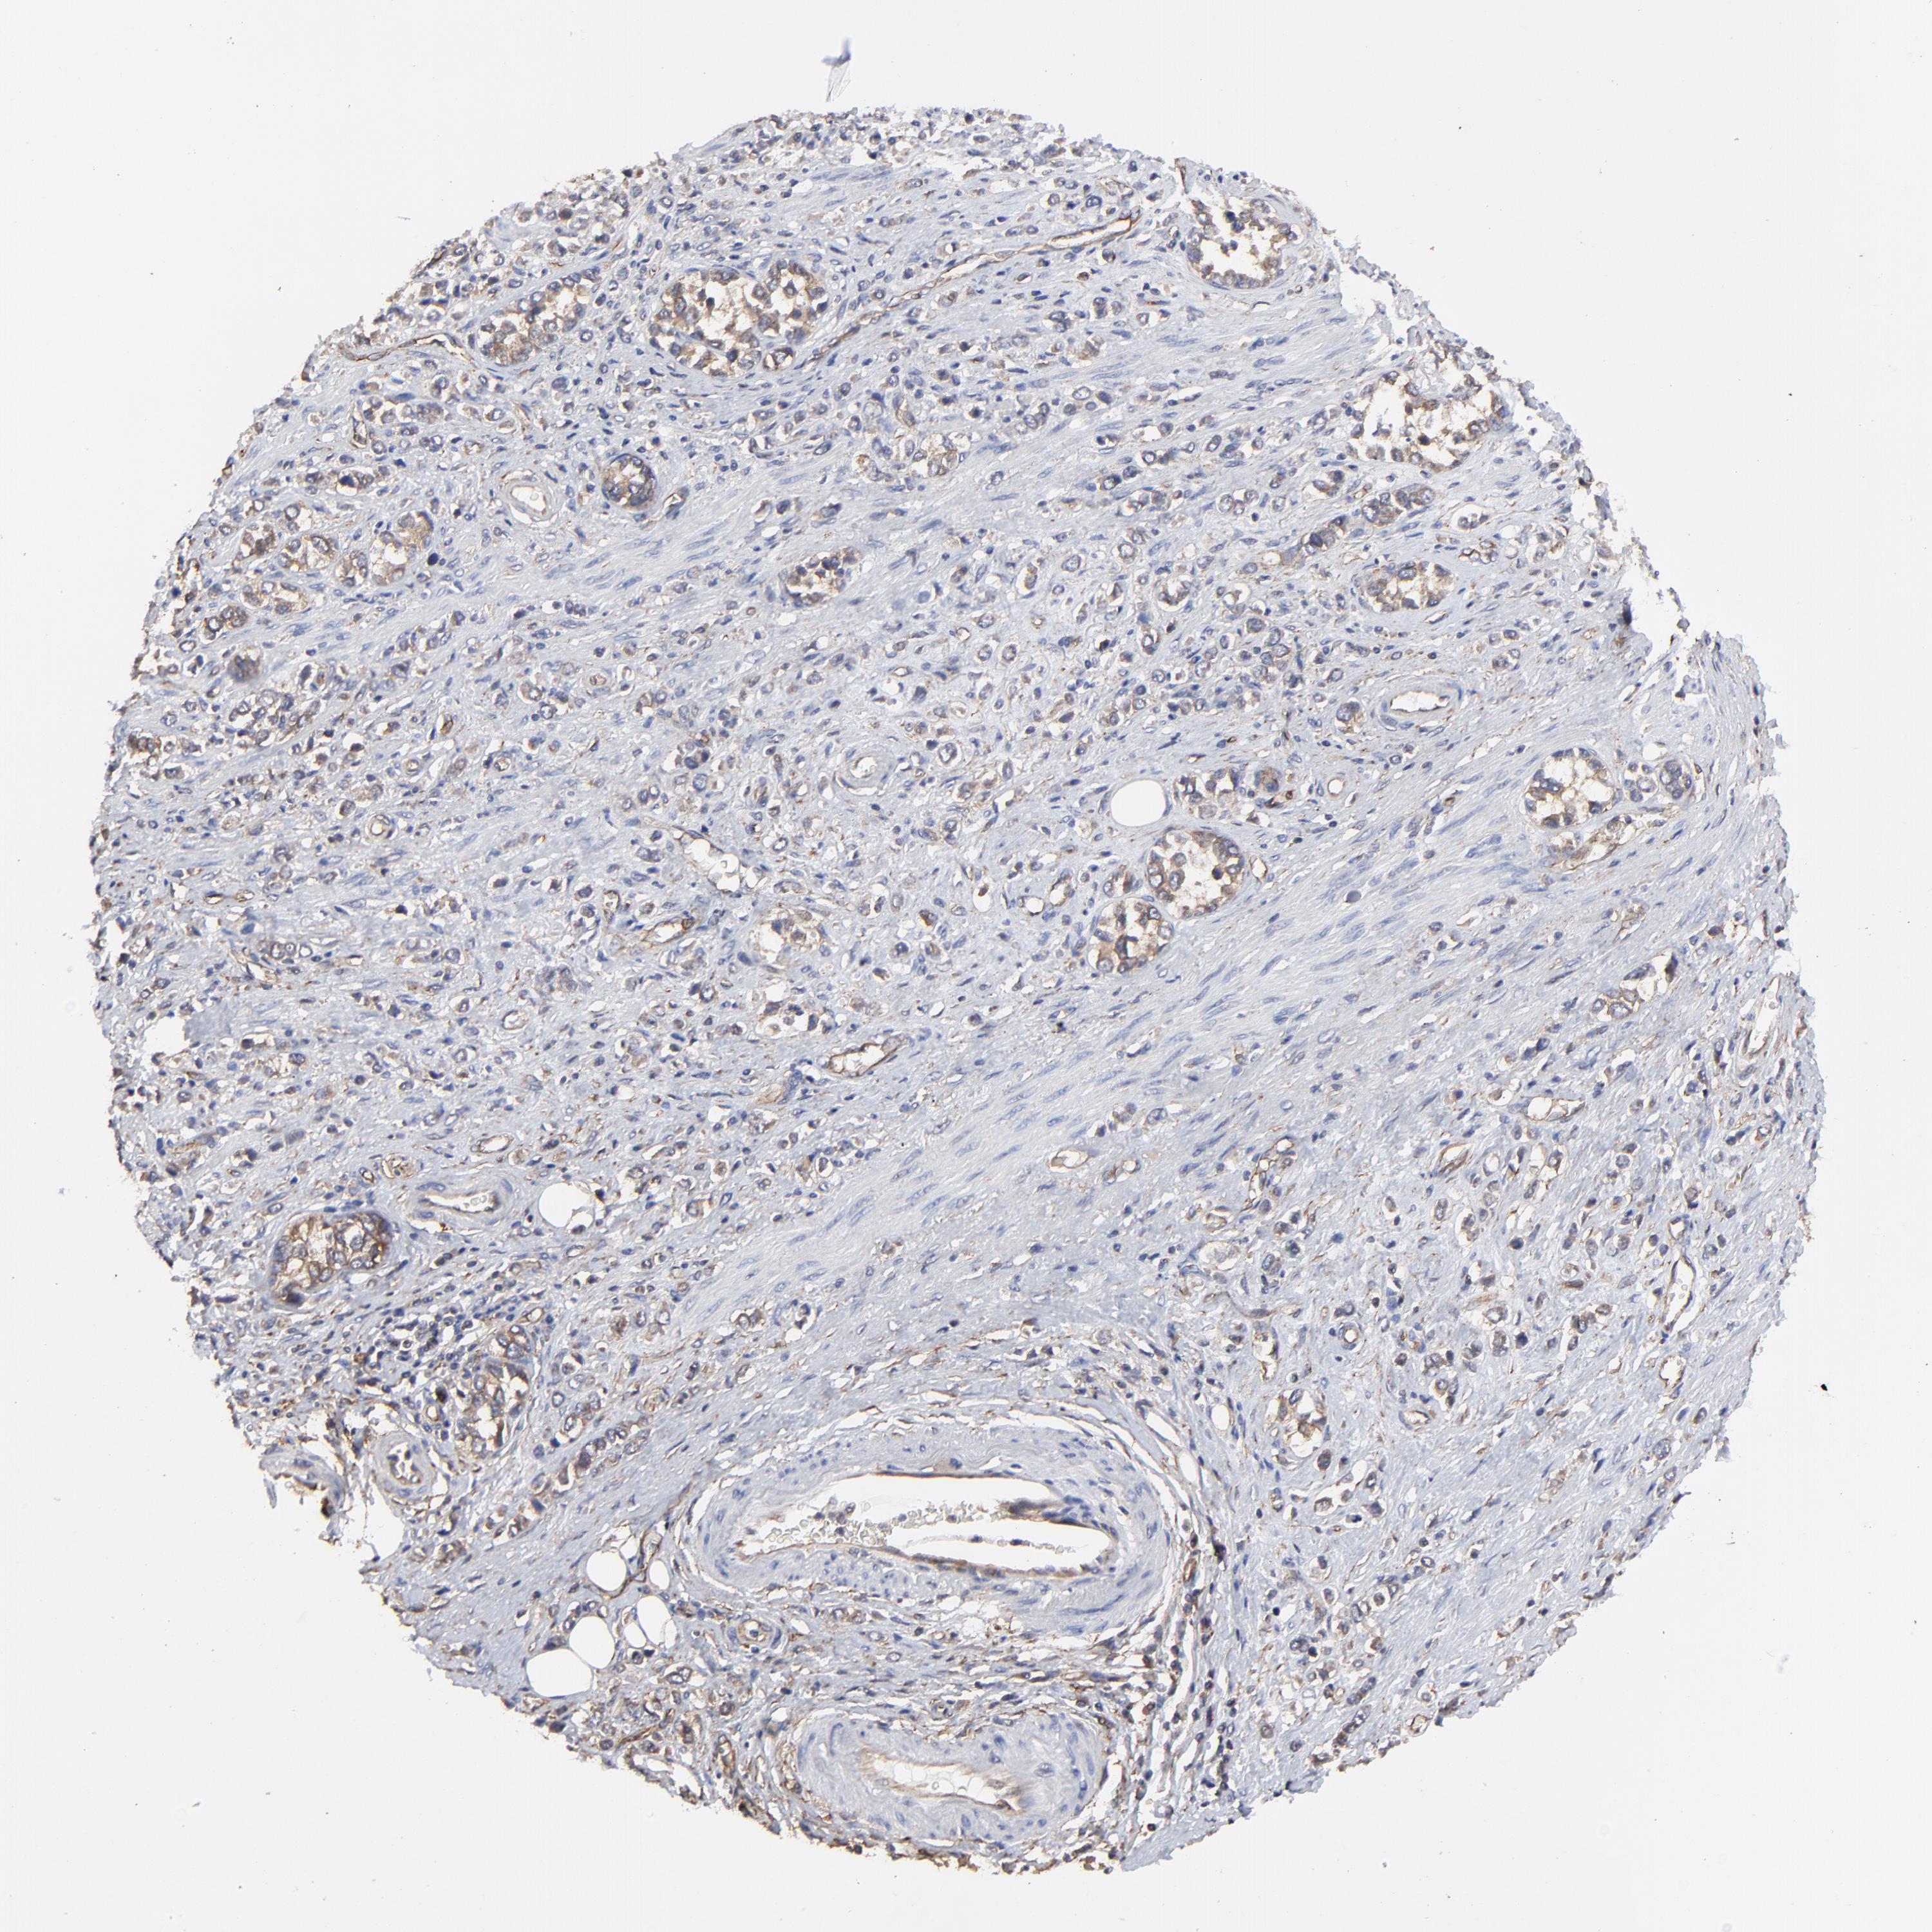

STOMACH CANCER - Protein expressioni

A mouse-over function shows sample information and annotation data. Click on an image to view it in a full screen mode. Samples can be filtered based on level of antibody staining by selecting one or several of the following categories: high, medium, low and not detected. The assay and annotation is described here.

Note that samples used for immunohistochemistry by the Human Protein Atlas do not correspond to samples in the TCGA dataset.

Antibody stainingi

Antibody staining in the annotated cell types in the current human tissue is reported as not detected, low, medium, or high, based on conventional immunohistochemistry profiling in selected tissues. This score is based on the combination of the staining intensity and fraction of stained cells.

Each image is clickable and will lead to virtual microscopy that enables deeper exploration of all samples and also displays staining intensity scores, fraction scores and subcellular localization as well as patient and tissue information for each sample.

Antibody HPA003004

Antibody HPA005819

Staining

High

Medium

Low

Not detected

Intensity

Strong

Moderate

Weak

Negative

Quantity

>75%

75%-25%

<25%

None

Location

Nuclear

Cytoplasmic/membranous

Cytoplasmic/membranous,nuclear

Adenocarcinoma, NOS